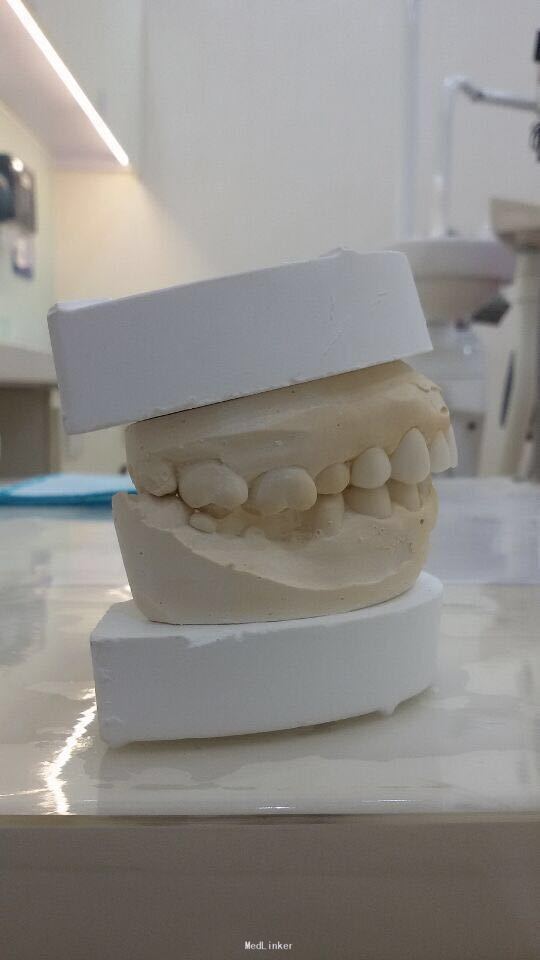

11 12 21 22死髓牙,不良修复体,牙龈炎 36 37 46 47残根 牙列不齐 处置:全口洁治。 比色,拍照,取模型做蜡型。 拆除旧修复体,拆桩核,做根管治疗,纤维桩修复,牙体预备,取模,做临时冠,粘固。11 12 21 22全瓷冠修复,13 14 23 24 31 32 33 34 41 42 43 44瓷贴面修复。